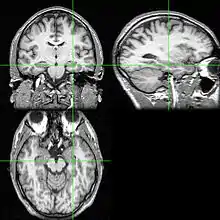

FMRI showing the active areas of a schizophrenic participant's brain while performing working memory tasks

Confabulation is the involuntary false remembering of events and can be a characteristic of several psychological diseases such as Korsakoff's syndrome, Alzheimer's disease, schizophrenia and traumatic injury of certain brain structures.[36] Those confabulating don't know that what they are remembering is false and have no intent to deceive.[37]

In the regular process of reconstruction, several sources are used to accrue information and add detail to memory. For patients producing confabulations, some key sources of information are missing and so other sources are used to produce a cohesive, internally consistent, and often believable false memory.[38] The source and type of confabulations differ for each type of disease or area of traumatic damage.